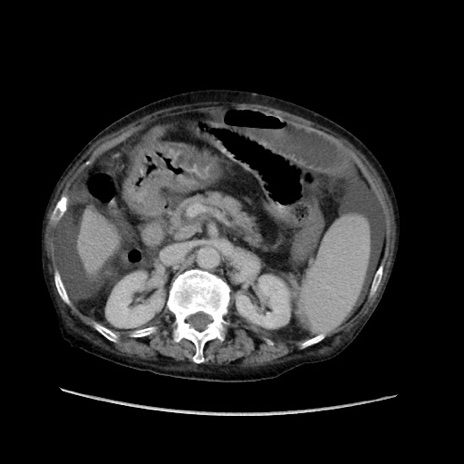

症例31(横断像)

【症例】80歳代 女性

【主訴】腹部膨満感

【現病歴】他院にて肝硬変にてフォロー中。1週間前から便秘、腹部膨満感、臍部腫瘤あり受診となる。

【既往歴】肝硬変

【身体所見】腹部膨隆あり、皮膚変化なし、疼痛なし。

【データ】WBC 4600、CRP 0.25